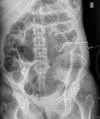

AXR: sentinel loop, pancreatic calcification